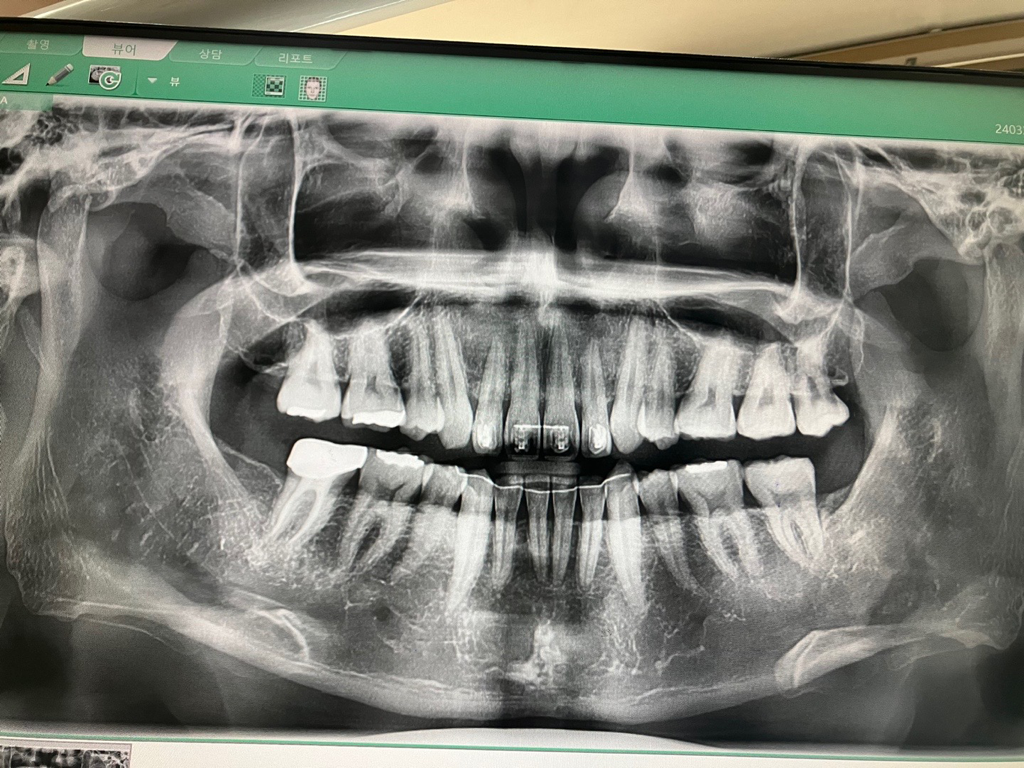

골격성 low angle? high angle?

안녕하세요.

교합고경에 대해서 알아보다가

low anlge , high angle 에 대해서 알게 되었는데요.

저는 low angle에 해당하는 건가요?

단순 파노라마 사진 보고는 골격의 양상을 파악하기 어렵습니다. 파노라마는 평면상에서 왜곡된 사진이기 때문에 그렇습니다.

더 정확히 알기 위해서는 교정 분석용 ceph 사진이 필요합니다.

파노라마 상으로는 분석을 할수 없습니다. 다른 방사선 사진을찍어서 분석을 해야 알수 있습니다.